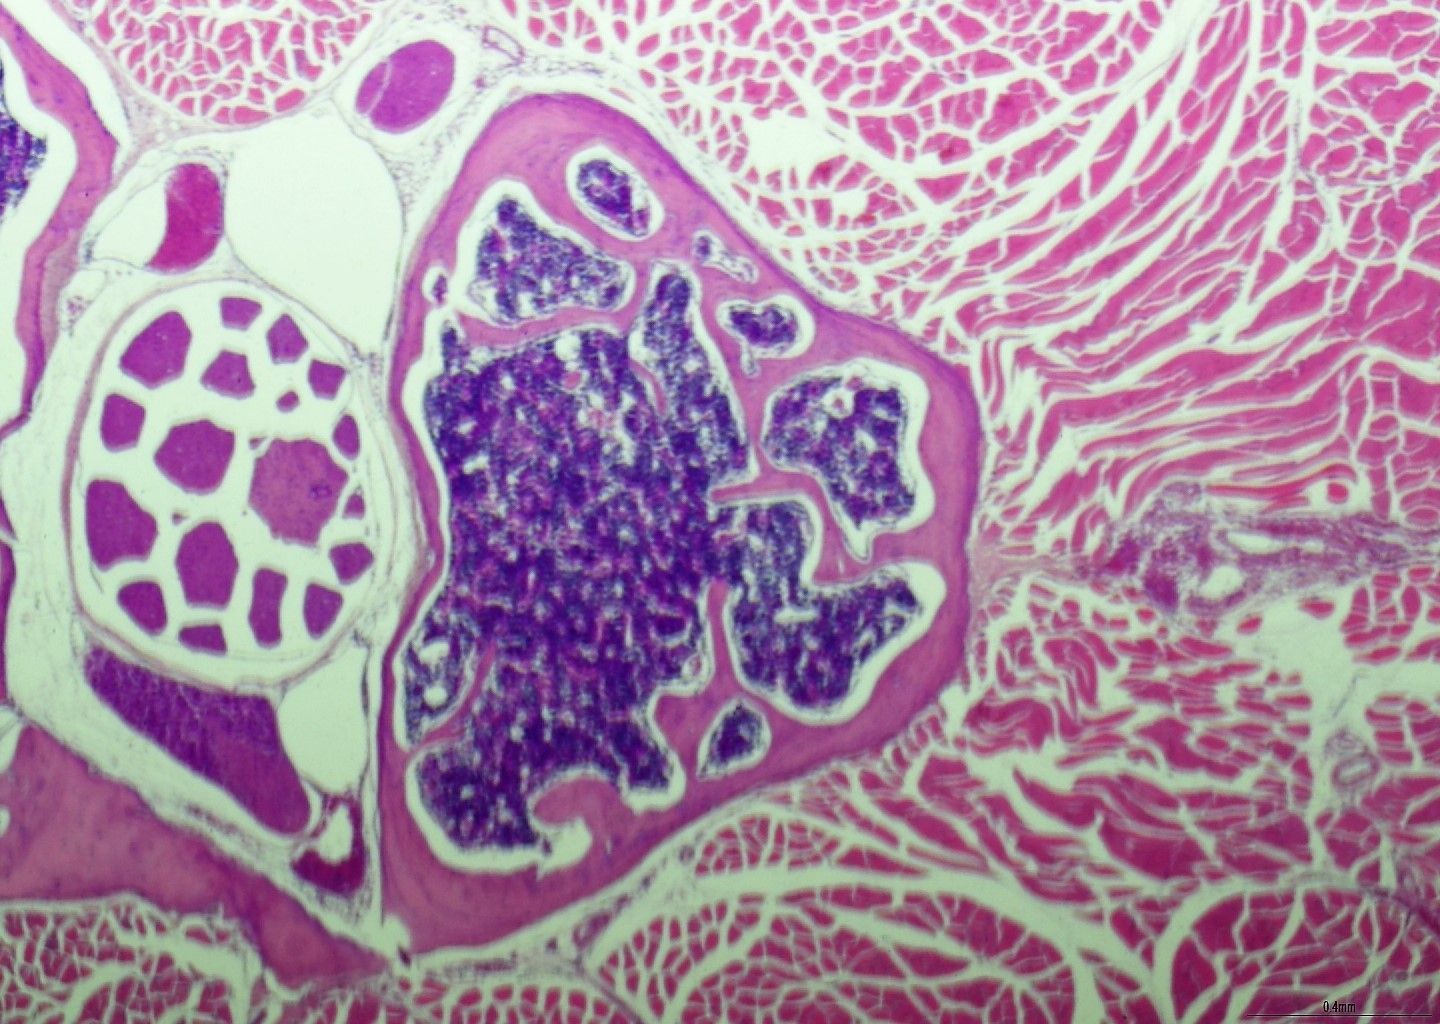

- Demonstracija specifičnih ciljeva krvnih stanica unutar biopsije BMT-a

- Dijagnostički polutanki rezovi smole